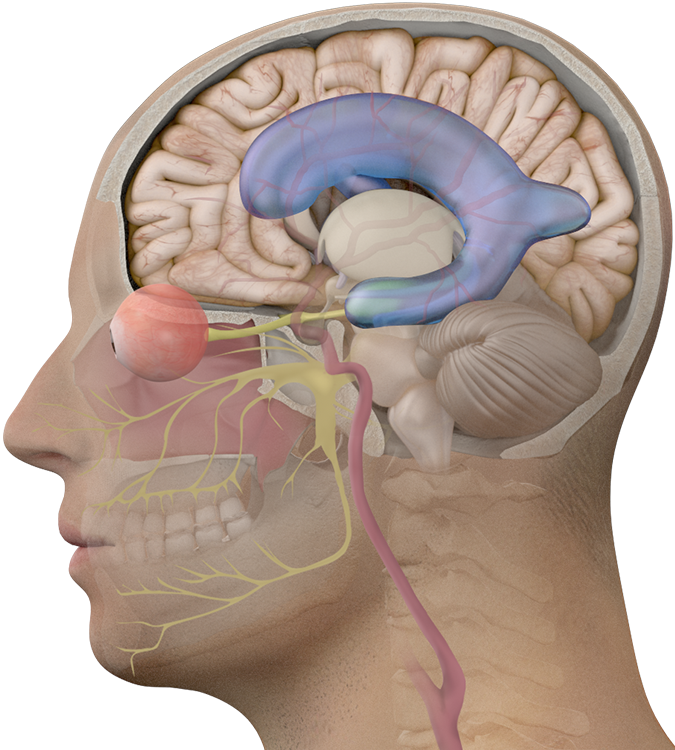

Вентрикуло-перитонеальный шунт: Показания и применение